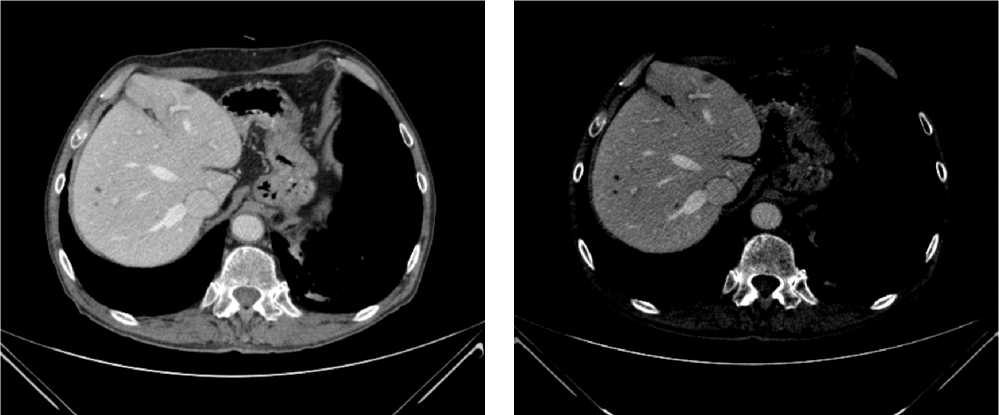

С июля 2022 г. у пациента отмечено появление эпизодов субфебрильной лихорадки. По результатам КТ органов брюшной полости от 08.2022 г. в проекции селезенки выявлена неоднородная инфильтрация с включениями, воздушной полостью в структуре, с тенденцией к отграничению и с распространением в параколическую клетчатку размерами 125 × 98 × 96 мм. Опухоль распространяется на большую кривизну желудка, вызывая утолщение стенки толщиной до 37 мм. По передней брюшной стенке справа отмечается округлое образование размерами 10 × 9 мм (рис. 5).

Рис. 5. Результаты компьютерной томографии органов брюшной полости у пациента 62 лет с диагнозом метастатический колоректальный рак с признаками микросателлитной нестабильности (август 2022 г., до лечения)

Fig. 5. Results of a CT scan of the abdomen of a 62-year-old patient with metastatic MSI-H colorectal cancer (August 2022, before treatment)

По решению мультидисциплинарной комиссии, с учетом выявленного прогрессирования заболевания, его распространенности (массивный опухолевый конгломерат в левом подреберье, вовлекающий близлежащие петли кишки и дистальные отделы желудка, поджелудочную железу), ограничивающей проведение хирургического лечения, биологического статуса опухоли (dMMR/MSI-H), соматического статуса пациента ECOG-2 (обусловлен болевым синдромом), рекомендована 1 линия иммунотерапии пембролизумабом.

С 12.10.2022 пациенту выполнено 15 введений пембролизумаба с промежуточным эффектом частичный регресс.

По результатам КТ органов брюшной полости (ОБП) от 08.2023, поддиафрагмально слева сохраняется инфильтрат 79 × 46 мм, распространяется на большую кривизну желудка, брюшину, диафрагму слева и по левому фланку брюшной полости. Желудок деформирован, стенки утолщены. Парагастральная и внутрибрюшинная клетчатка слева инфильтрирована. По брюшине сохраняются образования. Эффект лечения оценен как частичный регресс (рис. 6).

Рис. 6. Частичный регресс, по данным компьютерной томографии органов брюшной полости, на фоне иммунотерапии пембролизумабом у пациента 63 лет с диагнозом метастатический колоректальный рак с признаками микросателлитной нестабильности (август 2023 г.)

Fig. 6. Partial regression according to abdominal CT scan during immunotherapy with pembrolizumab in a 63-year-old patient with metastatic MSI-H colorectal cancer (August 2023)